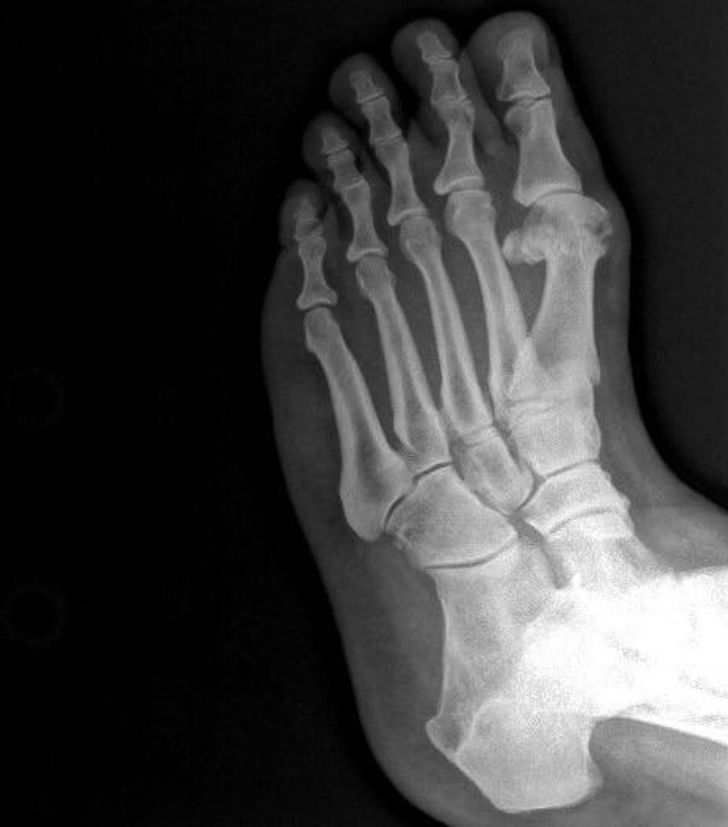

12. Hexadactyly, the word for having an extra toe

Illustration de l'article : 14 X-ray images that reveal a hidden story

© DomnLee / Reddit